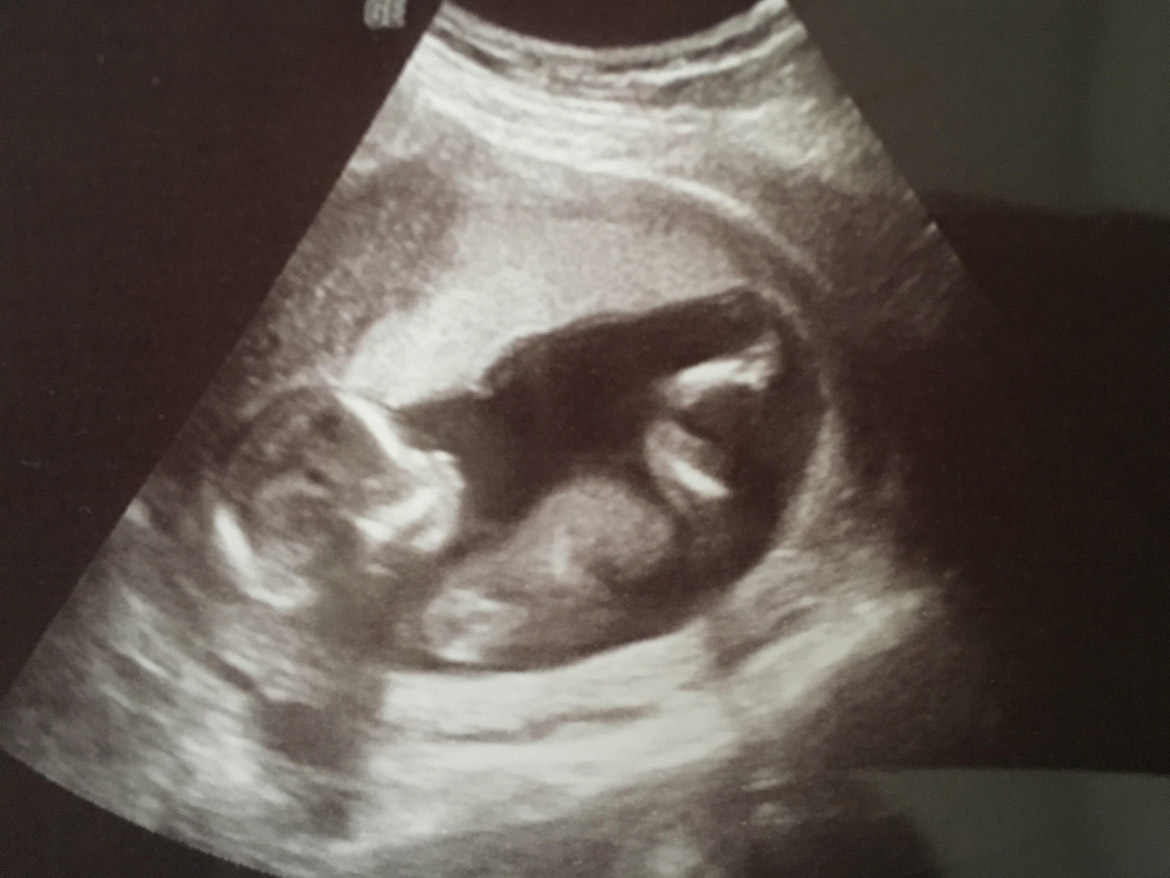

Steerman begins with a photo of the real scan (you keep your precious original) – snapped with your phone or scanned and sent to her. Then you will both chat about things like style and colours, so that you can beautifully capture and reflect your baby, your personalities, parenthood and the pregnancy. Your ideas are a big part of the process – whether it’s to do with matching the colours of the room it will be displayed in or gaining inspiration from a favourite image or photo.

“Some mums describe their baby full of personality, always kicking and moving about in the womb – those babies are painted with vibrant bold colours with plenty of movement,” she says. “Other mums describe their baby as placid and easy going so their painting suits pastels and more gentle paint strokes.”